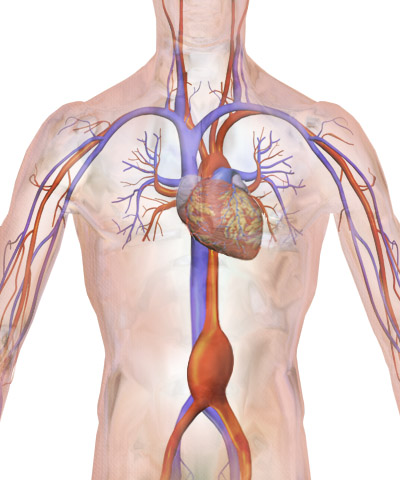

Männer über 65 Jahre haben ab 2018 einen Anspruch auf eine Ultraschalluntersuchung zur Früherkennung von Aneurysmen der Bauchschlagader (Aorta). Deutschland ist eines der letzten Länder in Europa, in denen ein solches Programm eingeführt wird. „Das Screening wird Leben retten“, ist Prof. Dr. Hubert Schelzig überzeugt. Er ist Direktor der Klinik für Gefäß- und Endovaskularchirurgie des Universitätsklinikums Düsseldorf (UKD). Das Team von Prof. Schelzig versorgt jährlich bis 150 Menschen, die an einer Aussackung der Bauchschlagader erkrankt sind.

Durch dieses Screening sollen Aneurysmen, also gefährliche Aussackungen der Schlagader, frühzeitig erkannt werden. Hintergrund: Reißt ein solches Aneurysma ein, überleben nur 20 Prozent der Patienten den massiven Blutverlust, der dadurch in kürzester Zeit eintritt. „Männer über 65 erkranken sechsmal häufiger als Frauen an einem Aneurysma der Bauchaorta. Zudem steigt das Erkrankungsrisiko mit dem Alter. Kommen weitere Faktoren hinzu, vor allem das Rauchen oder auch eine familiäre Vorbelastung, erhöht sich das Risiko noch weiter“, so der Gefäßexperte der Düsseldorfer Uniklinik.

Das Screening erfolgt per Ultraschalluntersuchung. Wird dort festgestellt, dass die Bauchschlagader gefährlich erweitert ist, kann schnell gehandelt werden. Dabei kann etwa operativ ein Ersatzgefäß in den erkrankten Bereich der Schlagader eingenäht werden. Eine schonende Alternative dazu stellt das minimal-invasive Einbringen einer Stentprothese über einen kleinen Leistenschnitt dar. Hierbei wird die Gefäßprothese unter Röntgenkontrolle exakt an die erforderliche Stelle geschoben und dort entfaltet. Auf eine große Operation kann so verzichtet werden.